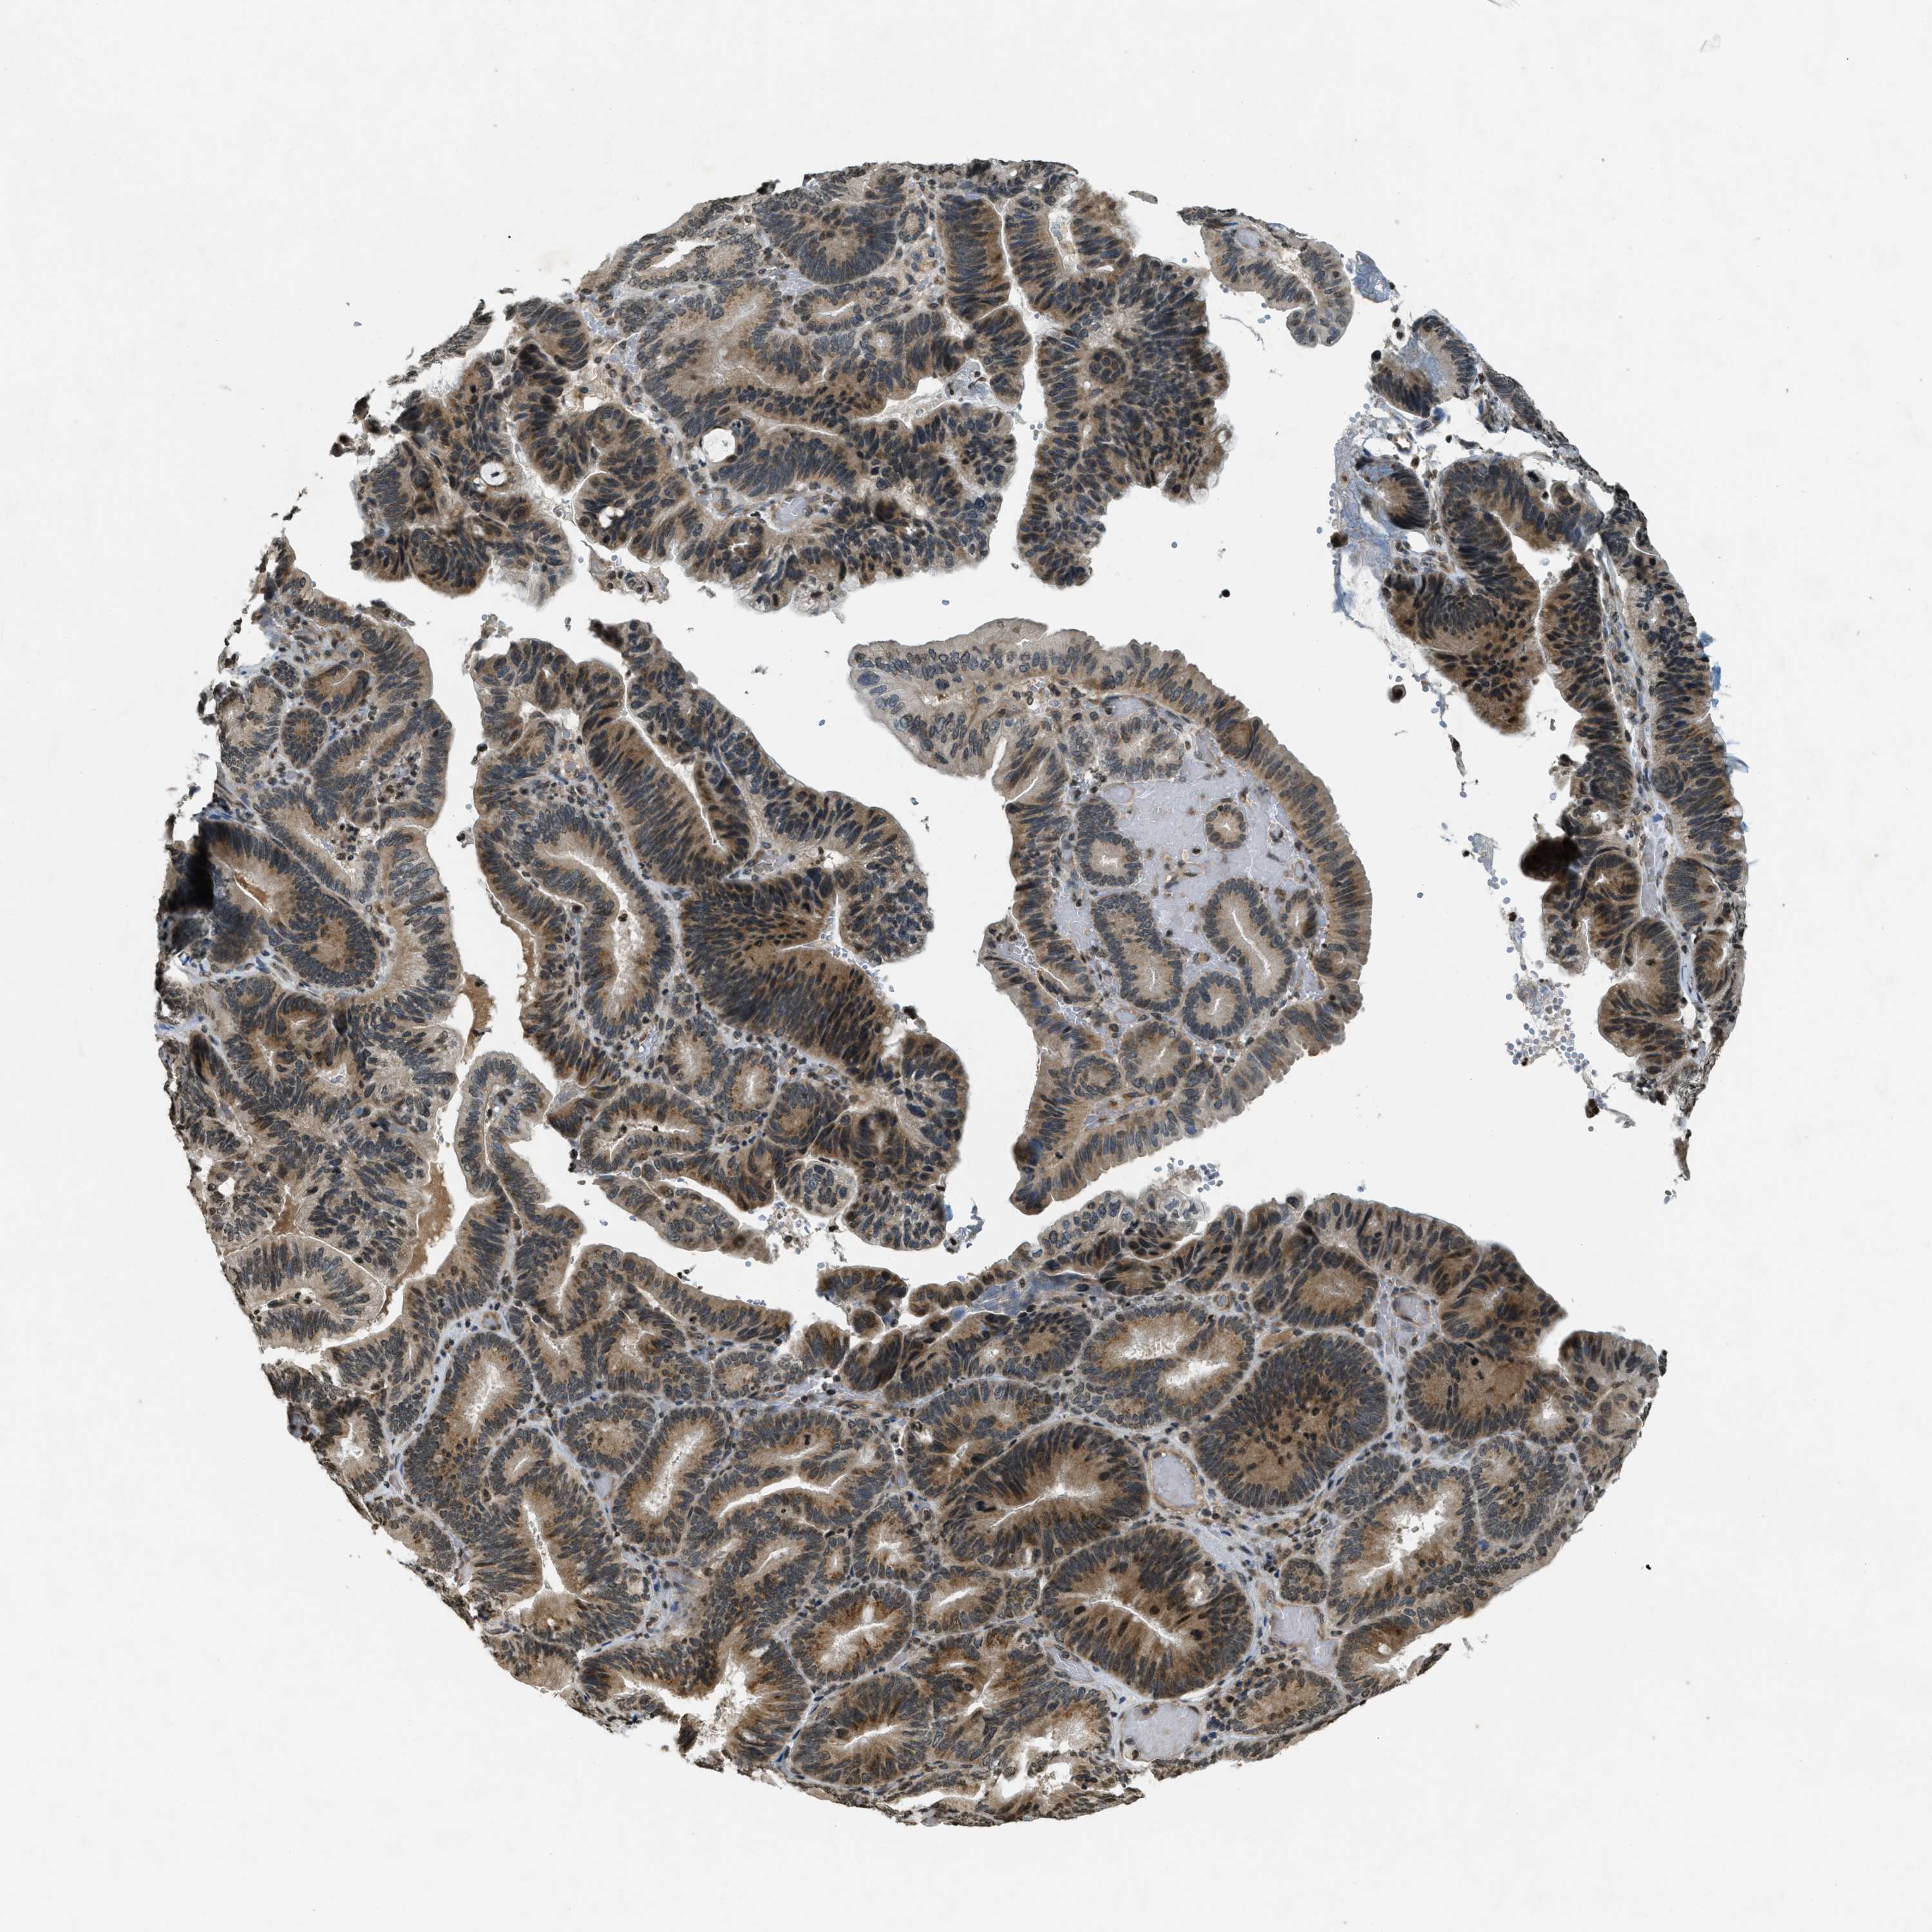

PANCREATIC CANCER - Protein expressioni

A mouse-over function shows sample information and annotation data. Click on an image to view it in a full screen mode. Samples can be filtered based on level of antibody staining by selecting one or several of the following categories: high, medium, low and not detected. The assay and annotation is described here.

Note that samples used for immunohistochemistry by the Human Protein Atlas do not correspond to samples in the TCGA dataset.

Antibody stainingi

Antibody staining in the annotated cell types in the current human tissue is reported as not detected, low, medium, or high, based on conventional immunohistochemistry profiling in selected tissues. This score is based on the combination of the staining intensity and fraction of stained cells.

Each image is clickable and will lead to virtual microscopy that enables deeper exploration of all samples and also displays staining intensity scores, fraction scores and subcellular localization as well as patient and tissue information for each sample.

Antibody HPA004246

Antibody CAB018641

Adenocarcinoma, NOS

Adenocarcinoma, metastatic, NOS